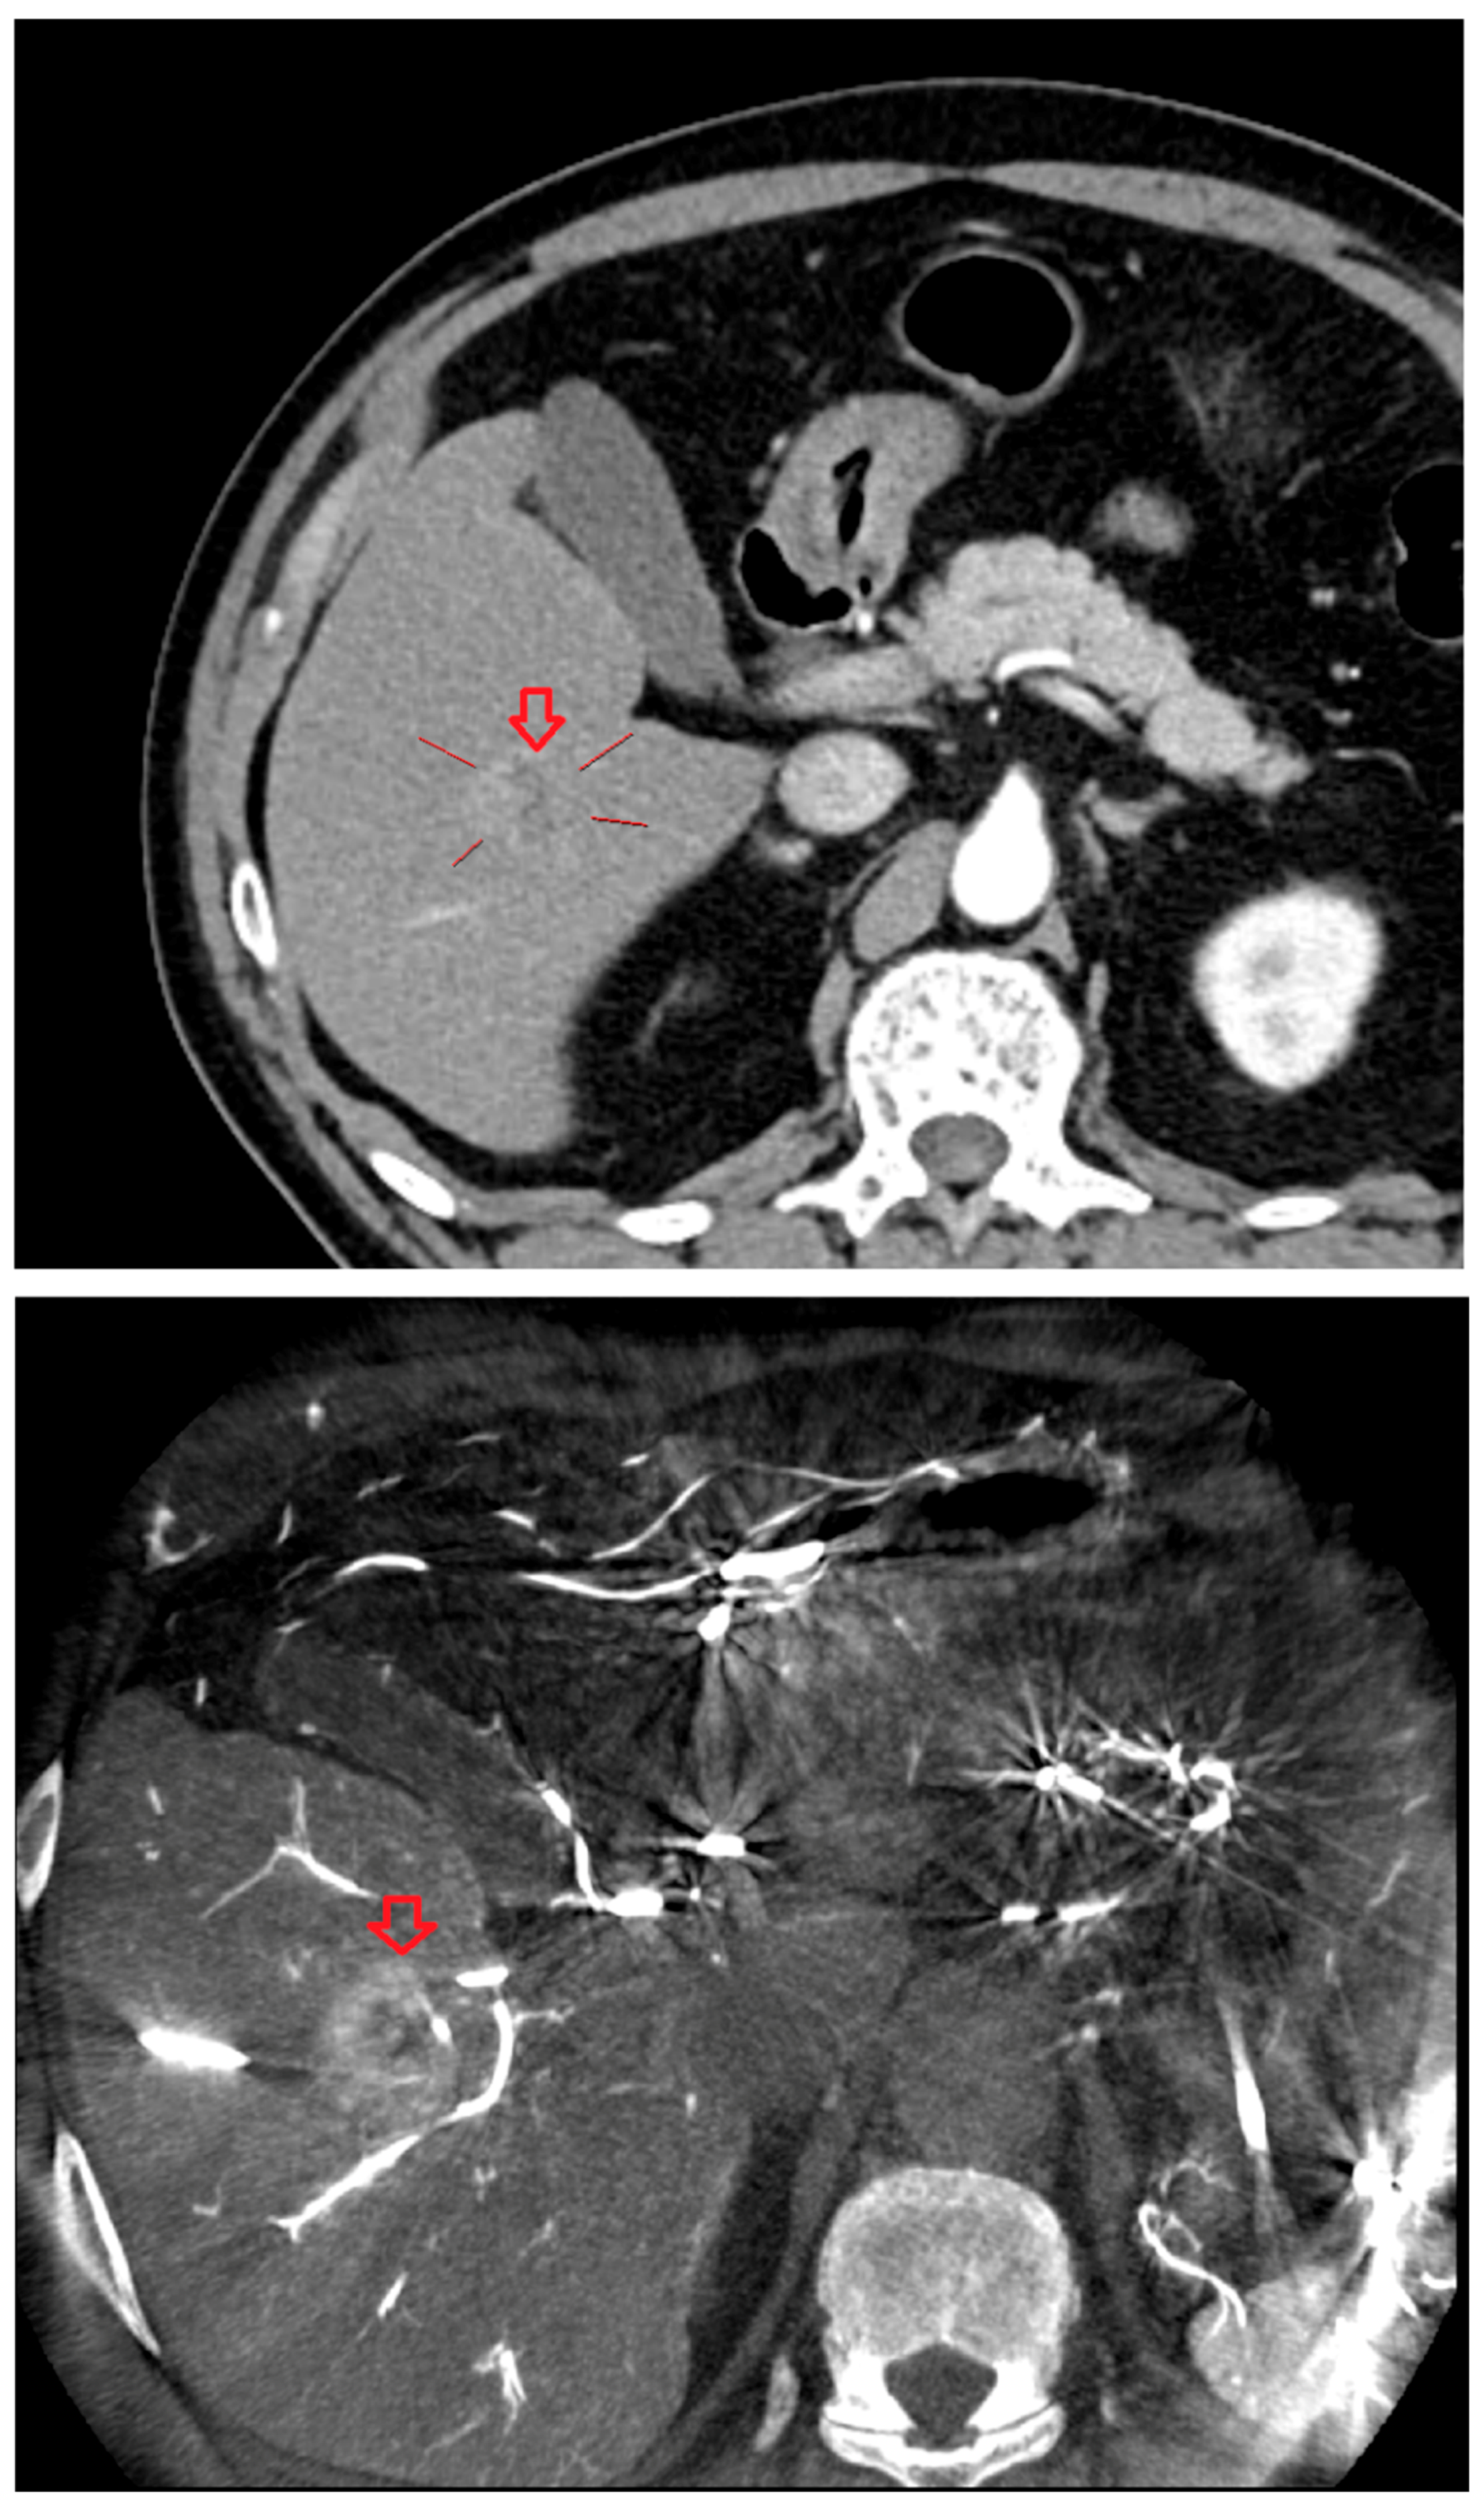

As shown in Figure 1, angio-CBCT allows for higher visibility of the target mass, as reflected in the ΔHU values. This can be visually confirmed in several cases. Representative cases in Figure 2 and Figure 3 demonstrate how the target mass is much more conspicuous to the operator on angio-CBCT compared to pre-procedural CT. In Figure 4, a mass, which was nearly invisible on pre-procedural CT, was identified through angio-CBCT, aiding the targeting process. Figure 5 shows a case where a mass with discordance between USG and CEUS was confirmed using angio-CBCT, leading to needle repositioning and achieving complete ablation. Finally, Figure 6 illustrates a case where a residual tumor was identified on angio-CBCT and re-ablation resulted in complete ablation.

Figure 3. CT images from other patient with hepatocellular carcinoma undergoing angio CBCT-guided RFA. (Top): pre-procedural CT (arterial phase). Red arrow and line = HCC mass (lesion 74.29 HU). (Bottom): intraprocedural angio CBCT. Red arrow = HCC mass (lesion 368.49 HU). ΔHU = 173.9 HU. (intra lesion − intra background) − (pre lesion − pre background).